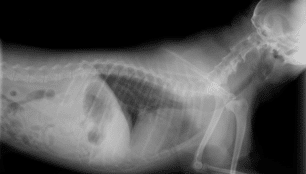

Diagnostic Imaging

Diagnostic imaging allows our veterinarians to diagnose illness, disease and other problems in order to prescribe the proper treatment